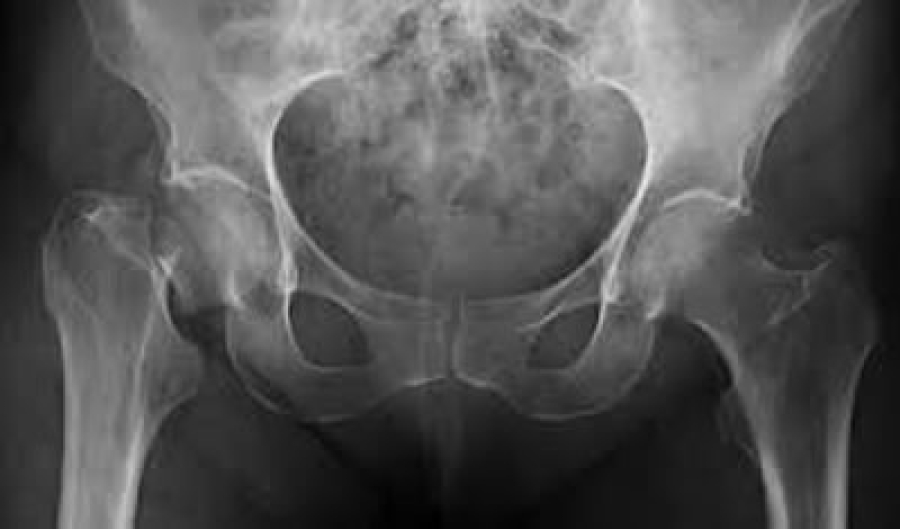

Aunque no podemos verlos ni sentirlos, nuestros huesos pueden estar cada vez más delgados y débiles. En todo el mundo, una de cada tres mujeres y uno de cada cinco hombres de 50 años o más se romperán un hueso debido a esta afección, de acuerdo con cifras de la Fundación Internacional de Osteoporosis IOF por sus siglas en inglés.

La osteoporosis es una “enfermedad silenciosa” que torna los huesos tan frágiles que pueden romperse, incluso después de una pequeña caída o golpe; lo alarmante es que 80% de las personas que sufren una fractura por esta condición no son diagnosticadas ni tratadas, indican los datos de IOF.

La osteoporosis es una enfermedad poco diagnosticada y tratada porque no tiene síntomas. Muchas personas desconocen que padecen esta enfermedad hasta que sufren la primera fractura. En todo el mundo, millones de personas en riesgo de fracturas, desconocen la enfermedad subyacente.

El vínculo entre la osteoporosis, los huesos rotos y las graves consecuencias de las fracturas son poco conocidas. Además, la importancia de una buena salud ósea es subestimada con demasiada frecuencia, y por lo tanto descuidada, por los pacientes y por los médicos. A nivel de salud pública, muchos gobiernos y autoridades de salud desconocen la enorme carga socioeconómica causada por la osteoporosis y las fracturas por fragilidad.